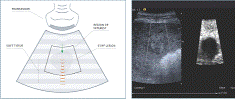

На рисунке 3, исследование

производилось в В-режиме на линейном датчике, и как видно слева - нет ничего

особого, что могло бы привлечь внимание исследователя, но когда включается

режим эластографии, совершенно четко видны потенциально патологические

включения. В данном исследовании использовался эластографический фантом, так

что на практике дело обстоит несколько иначе и раковые образования крайне редко

имеют такую правильную форму - а это уже определенные трудности при

сканировании (Рис. 4).

Рис. 3. В-изображение (слева), тот

же самый участок исследования, но с окном построения эластограммы (справа)

Рис. 4. Инфильтративный рак молочной

железы (выделено синим)